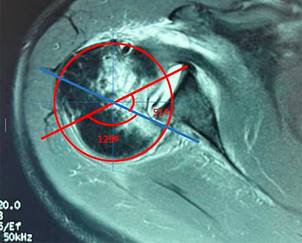

En consulta (ocho semanas desde el accidente), se apreció al paciente con dolor intenso en el hombro derecho (EVA 7/10). A la exploración física del hombro derecho, se observaron arcos de movilidad limitados: flexión 60o, abducción 40o, extensión 15o, aducción 10o, rotación externa 5o. Se solicitó resonancia magnética (RM) simple de hombro derecho, la cual evidenció luxación posterior enganchante de hombro derecho, Hill-Sachs reverso y lesión de subescapular ISAKOS anterior II. Tras la confirmación del diagnóstico, se documentó una fractura por impresión de la cabeza que involucraba el 28.3% de la circunferencia cartilaginosa, sin fracturas relevantes del borde glenoideo posterior. El tamaño del defecto de la cabeza humeral se midió en la RM en un corte axial, justo por debajo de la coracoides. Se colocó un círculo sobre la cabeza humeral y se trazaron líneas que definieron ángulos clave para medir el porcentaje de la superficie articular afectada, con el porcentaje del ángulo del cartílago representando el 100% de la superficie articular y el ángulo del defecto indicando el tamaño estimado del defecto de la cabeza humeral (Figura 1). A las nueve semanas después de la lesión, se realizó tratamiento quirúrgico con reducción abierta y transferencia de subescapular mediante técnica McLaughlin modificada.

Figura 1: El tamaño del defecto óseo se calculó en la resonancia magnética, en un corte tomado inmediatamente inferior a la punta de la apófisis coracoides. El porcentaje del ángulo de cartílago (180o en este caso) que representa el ángulo de defecto (51o) se estimó en 28.3%.

La RM y la TC, además de ayudarnos en el diagnóstico, son de gran utilidad para ayudar al cirujano a analizar la localización y evaluar el porcentaje de pérdida ósea, tanto en la cabeza humeral como en la glena. La RM o la TC son necesarias para evaluar dicho porcentaje, lesiones asociadas y orientar al cirujano hacia la mejor opción de tratamiento.11 Gerber y colaboradores proponen un método para la medición del defecto óseo en RM o TC; en la RM se mide en un corte axial a nivel de la apófisis coracoides o inmediatamente por debajo de la misma, se coloca un círculo sobre la cabeza humeral, se traza una línea desde el centro del círculo hasta el cartílago inmediatamente adyacente a la tuberosidad menor y otra línea desde el centro del círculo hasta el extremo posterior del cartílago adyacente a la inserción del infraespinoso, esta área es el ángulo de superficie articular. Un segundo ángulo, el ángulo del defecto, es el ángulo formado por las líneas que conectan, primero, el límite anterior y, segundo, el límite posterior del defecto con el centro de la cabeza humeral. El porcentaje del ángulo del cartílago representa el 100% de la superficie articular y el ángulo del defecto es el tamaño estimado del defecto de la cabeza humeral.12